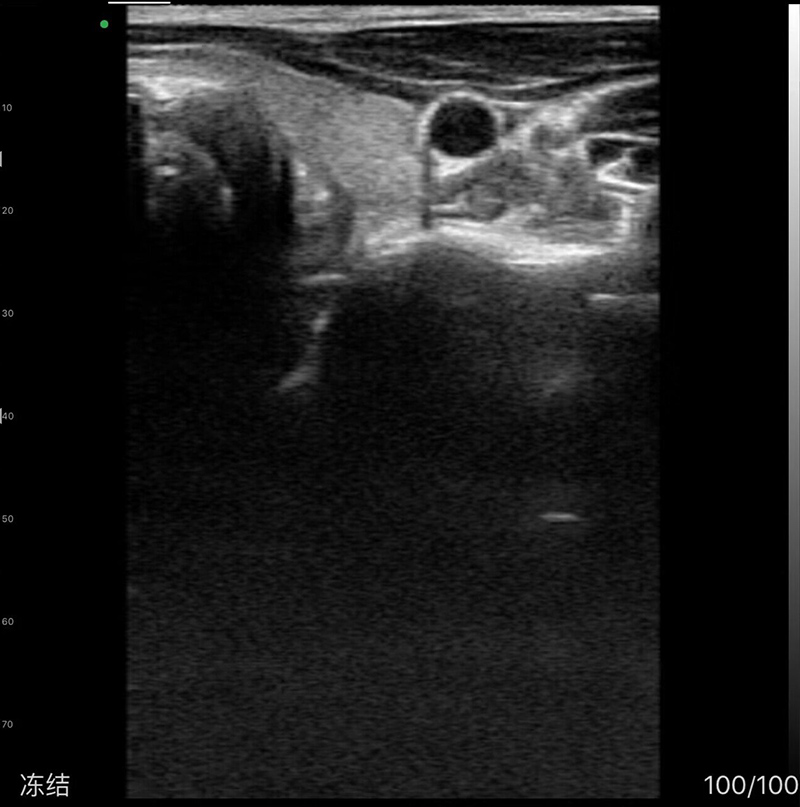

• 探头频率、扫描深度:6.5MHz/8MHz, 40-100mm

• 显示模式:B、B/M,彩超、PW、PDI

• 图像调节:增益、焦点、反相脉冲谐波、降噪

• 电影回放:手动和自动回放,可设置回放帧数为100/200/500/1000

• 图像帧频:18f/s

• 穿刺辅助功能:平面内穿刺引导线功能,平面外穿刺引导